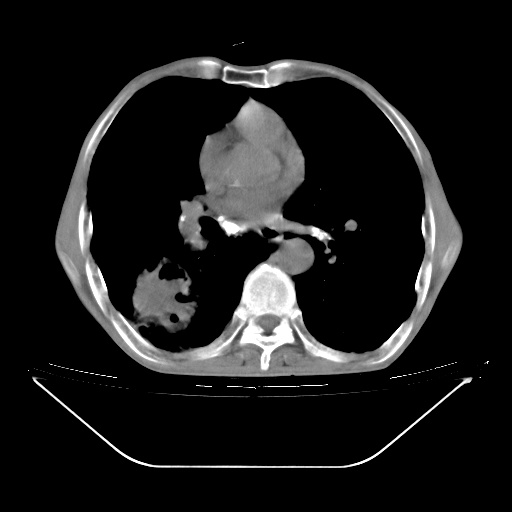

以下是引用zsl6918在2008-8-25 21:55:00的发言:[br]符合右肺周围性肺癌并肺内转移,左肺结核球。双肺肺气肿。腰椎附件转移。

以下是引用随光逐影在2008-8-25 22:03:00的发言:[br]1)考虑右肺下叶周围性肺癌并肺内转移,腰椎附件转移。2)左上肺结核(结核球形成)。3)双肺肺气肿(多发肺大泡形成)。4)双肺门区及纵隔内多发淋巴结钙化。